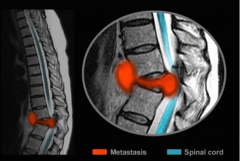

椎间盘椎间盘是椎体连接的重要组成部分,由于它具有很强的柔韧性,不但可以使脊柱活动的灵活性得到加强,有效地减缓了人在行走、跳跃时来自地面的冲击力,保护脑和重要脏器免受剧烈......【点击详情】